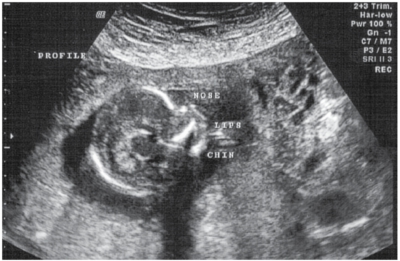

Progresele formidabile, cu adevărat impresionante realizate în domenii precum genetica, ultrasonografia fetală (ecocardiografia şi neurosonografia fetală) sau medicina perinatală au adus numeroase beneficii atât pentru pacienţi cât şi pentru medicii practicieni, însă au generat şi numeroase controverse şi probleme de bioetică. Din această cauză etica reprezintă o dimensiune esenţială în medicina perinatală.

Trebuie menţionat încă de la început faptul că în contextul medicinei fetale pe de o parte, al diagnosticării prenatale pe de alta, şi nu în ultimul rând în cel al medicinei perinatale în general, noţiunile de embrion sau făt privit ca şi pacient sunt pe deplin justificate. Este corect din punct de vedere etic, medical şi ştiinţific ca produsul de concepţie uman care urmează să se nască, deci să capete personalitate şi individualitate proprie, să fie tratat ca şi pacient încă din viaţa intrauterină.

Managementul sarcinii prin prisma diagnosticului prenatal include atât screeningul cât şi diagnosticul genetic prenatal propriu-zis.